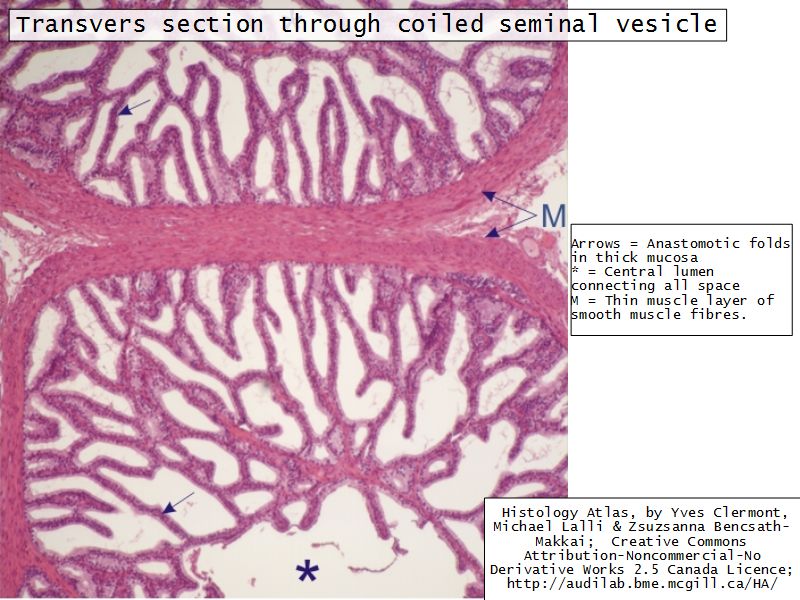

Vesicula seminalis

Slide 81Vesicula seminalis

- Mucosa

- Epithelium

- Lamina propria

- Muscle layer

Mucosa

- Lumen

- Irregular

- Store secretions

- Pseudostratified columnar epithelium

- Lamina propria

- Contains AVL

- Folded mucosa ^^ surface area

Muscle layer

- Inner circular

- Outer longitudinal